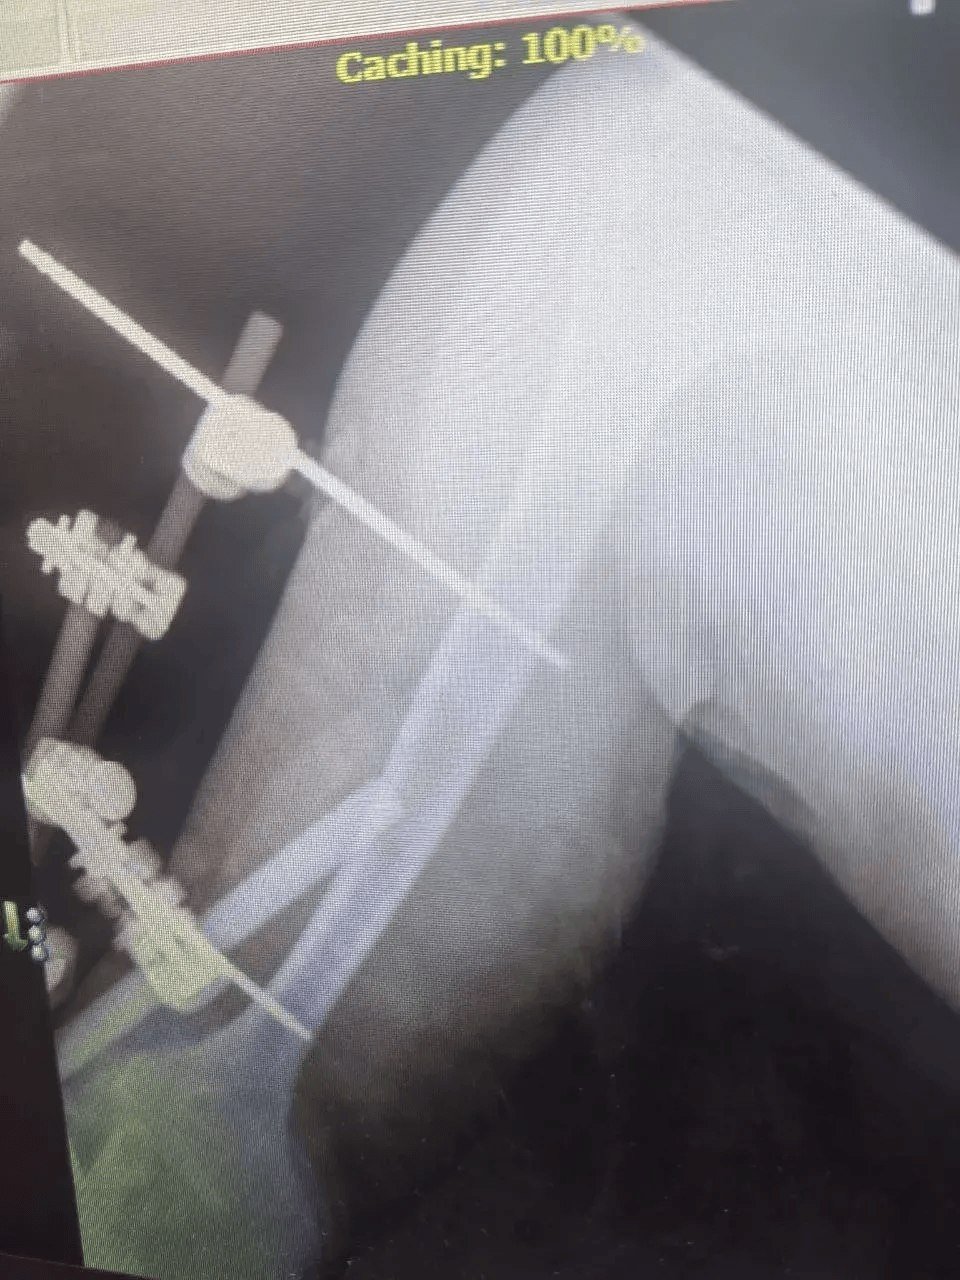

Мужчина 1972 года рождения получил множественные переломы и другие серьёзные травмы. Его лечением занималась команда специалистов разных профилей. Челюстно-лицевые хирурги провели шинирование, травматологи-ортопеды выполнили операцию на правой локтевой кости и восстановили левую лучевую. Также пациент проходил лечение у нейрохирургов и неврологов.